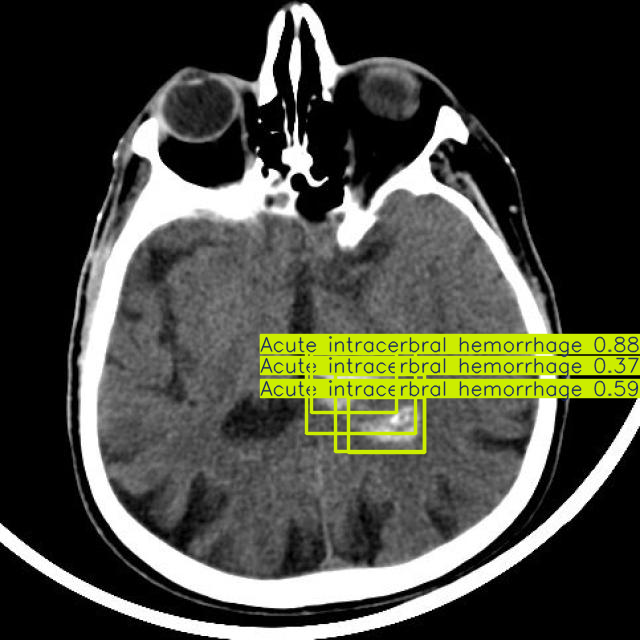

Brain Stroke Detection

Our AI model analyzes brain CT scans to quickly detect signs of stroke, enabling rapid treatment and improving patient outcomes.

Brain Stroke Image